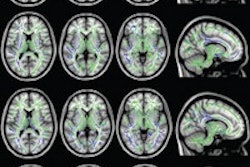

The upgrades include a new design for the company's Saturn gradients that increases performance and results in better image stability, as well as improvements in functional MRI performance.

Other upgrades are found in the company's mVox 3D isotropic imaging protocol, Time-SLIP arterial spin labeling protocol for noncontrast imaging of cerebral vascular circulation, 16-channel flex and medium large coils, and M-Power interface.